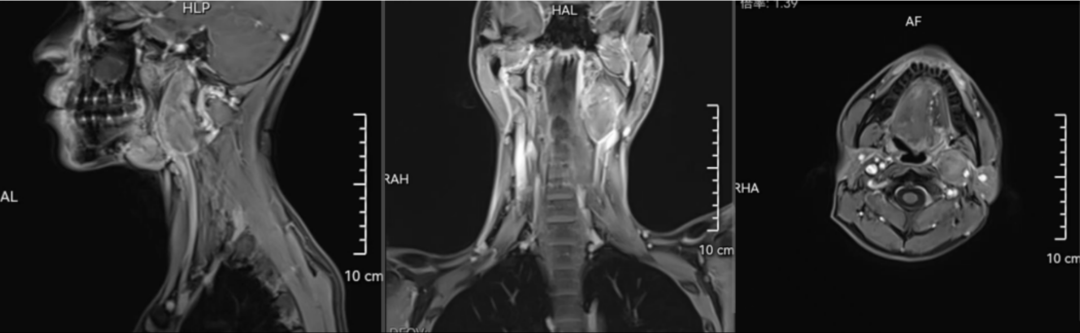

术前磁共振

“我们神经外科已把肿瘤切除干净,杨副主任该你了。”1月13日,第一师医院手术间内,神经外科医生和口腔—颌面外科正在联合为疑难患者开展手术,该患者是什么情况呢?为什么需要两个科室合作治疗?原来,32岁的艾尼瓦尔·艾尔肯(化名)长有一个神经鞘瘤,大小约6厘米,肿瘤侵犯神经导致左侧面部面瘫、声音嘶哑、吞咽困难。此类神经上衍发的肿瘤均属于神经外科治疗范畴,但患者肿瘤位置却在颈深部并向颅底蔓延,紧邻颈动脉、迷走神经、食道、咽后壁、腮腺等,这一位置又属于口腔—颌面外科治疗范畴,肿瘤较大,如此复杂的肿瘤让神经外科专家思考了许久:如何既保障肿瘤切除干净,又要尽可能保护患者正常的生理功能,不产生新的并发症?